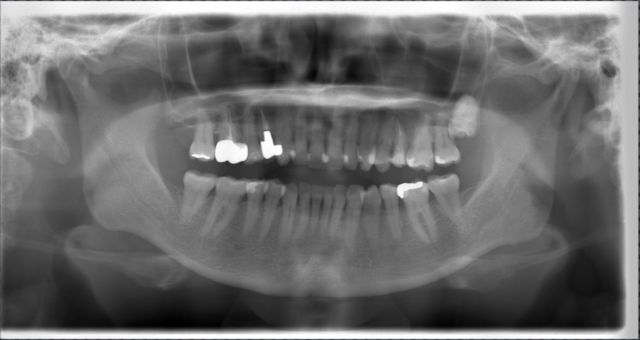

術前レントゲン

-